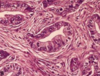

Microscopically, dense fibrosis and destruction of alveolar architecture.

Active fibrotic lesions composed of myofibroblasts

Aggregation of spindle cells with gray to pale purple matrix adjacent to dense fibrosis

Usual interstitial pneumonia (UIP) pattern